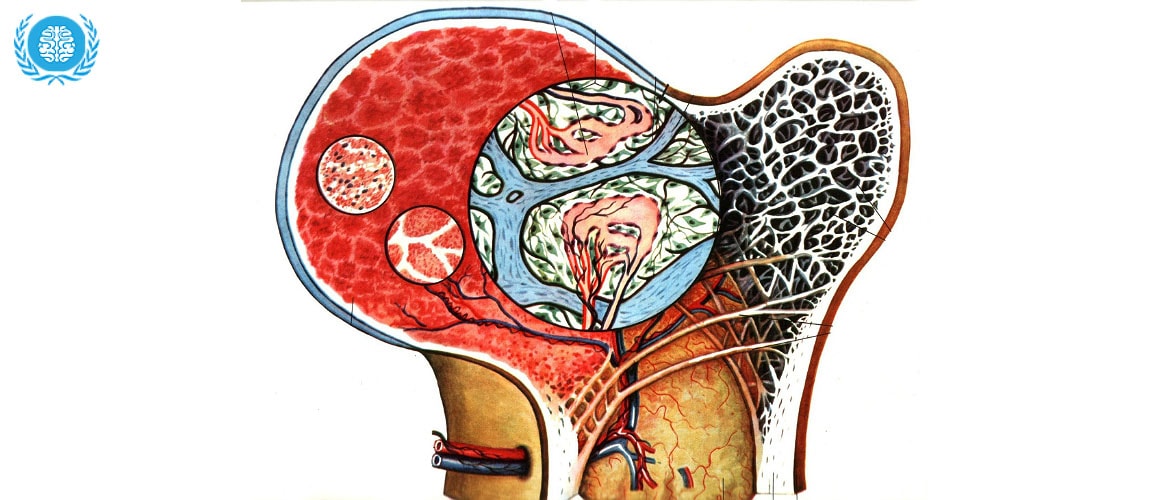

Изучение костного мозга: анатомия и функции